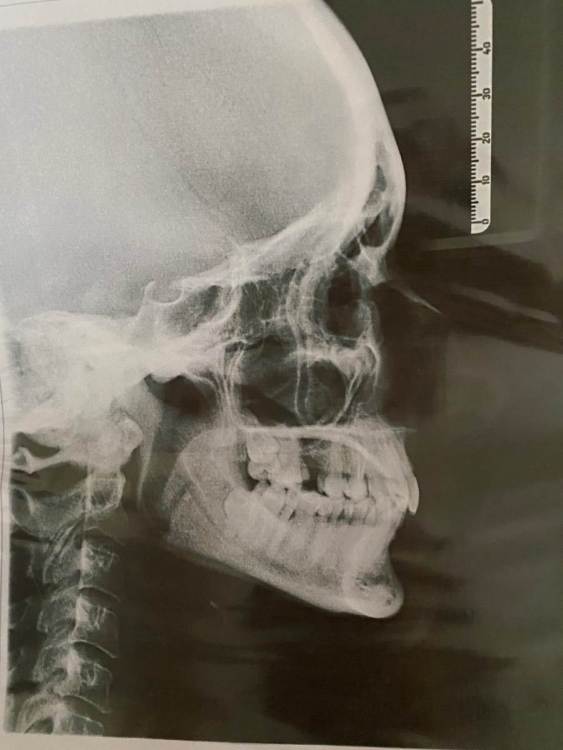

Подскажите, возможно ли перемещение верхних 8к на место 7к , а 7к на 6ки в моем случае? Я знаю, что это долго.

До пандемии я нашла двух врачей, которые уверенно сказали, что такое возможно. Далее, случилась пандемия и брекеты пришлось отложить) Придя недавно на консультацию мне вдруг оба заявили, что нет двигать не будет: долго, пазуха низко, вообще только имплант.

Еще меня беспокоит нижняя 8-ка, по кт в ее корнях проходит нерв, и как мне сказали, при удалении его повредят и будут разные последствия. Можно ли его оставить на месте?

48E17360-8D5A-44A6-BDD9-AED5CF673CA7.jpeg